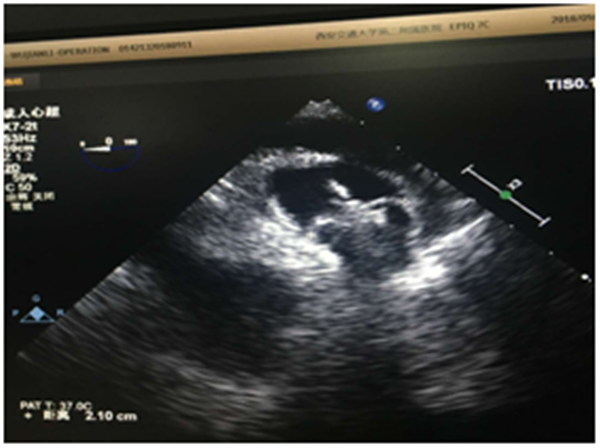

2018年9月11日,我院心血管病院郑强荪院长团队,心内科朱参战主任、张玉顺主任配合成功对一男性55岁患者进行了左心耳封堵术,该患者属非瓣膜性房颤,有多年房颤史且近期头晕,心慌症状加剧,不愿口服抗凝药,于9月10日经食道超声检查排除左心耳血栓,遂决定行左心耳封堵术。

术中TEE测量心耳大小00 18mm×30mm,450 20mm×33mm, 90018mm×30mm, 135017mm×18mm,DSA测量心耳开口22mm,深度27mm。 根据TEE及DSA测量的结果,综合考虑后,选用27mm WATCHMAN左心耳封堵器,伞器展开后,测量计算压缩比为19%-25%,牵拉稳定,满足PASS原则,释放器械,成功封堵。